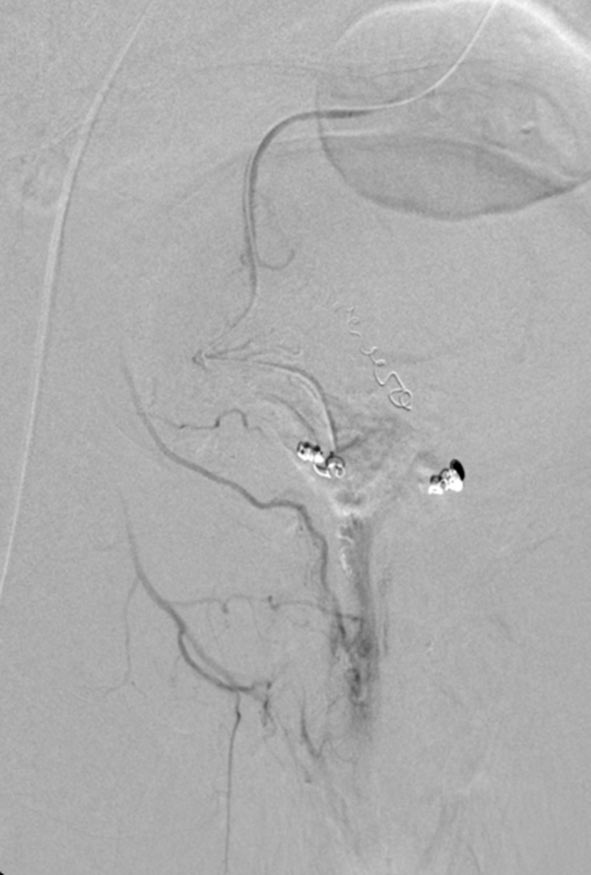

Drs. Mikin Patel & Osman Ahmed (@TheRealDoctorOs) & Layth Alkhani, BS, comment on the emergence of hemorrhoid artery embolization as a safe & effective option for those with symptomatic internal hemorrhoids, reviewing technique, patient selection, & more. evtoday.com/articles/2026-…